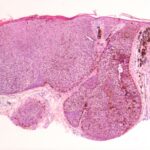

melanoacanthoma